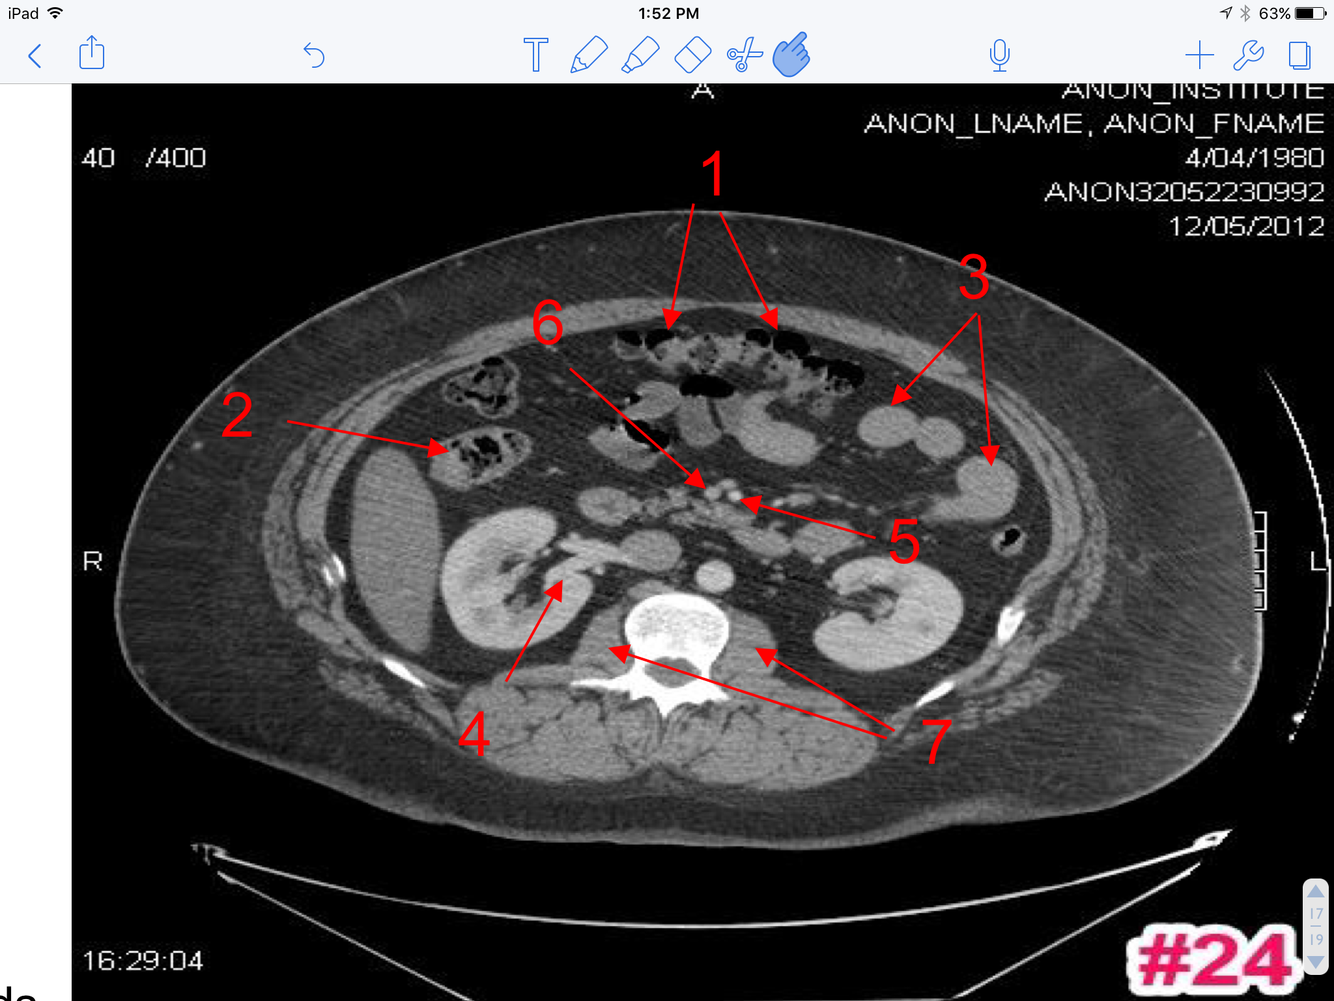

15

A

1. Transverse colon

2. Ascending colon

3. Loops of small bowel

4. Rt. renal V

5. Superior mesenteric A

6. Superior mesenteric V

7. Psoas major M